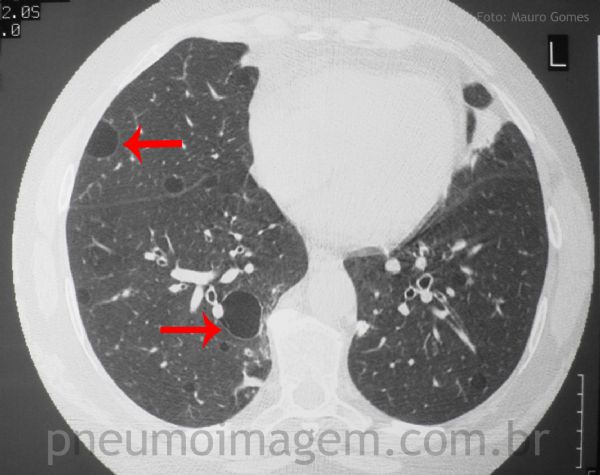

Os achados mais comuns na TC são opacidade em vidro fosco (seta amarela), consolidação e cistos de paredes finas (seta vermelha). Neste caso, as opacidades em vidro fosco estão associadas a nódulos centrolobulares (seta amarela), o que pode representar hiperplasia linfóide associada ao brônquio, compatível com bronquiolite folicular.

Pulmonary involvement affects about 10% of cases and may be the first manifestation of the disease, interstitial fibrosis and xerotraqueia are the most common. Obstructive bronchiolitis is a result of lymphocytic invasion of epithelium. The lymphocytic infiltrate in the parenchyma characterizes lymphocytic interstitial pneumonia (LIP, LIP) and has the most severe complication of the disease is pulmonary lymphoma. The most common CT findings are ground-glass opacity (yellow arrow), consolidation and thin-walled cysts (red arrow).

In this case, the ground-glass opacities appear to be associated with centrilobular nodules (yellow arrow), which may represent lymphoid hyperplasia associated with bronchus, compatible with follicular bronchiolitis. Keys: collagenosis; autoimmune disease.

The American-European Consensus establishes the criteria for the assessment of disease manifestations of sicca syndrome in the presence of autoantibodies anti-Ro (SSA) and anti-La (SSB) and histopathological findings of salivary glands. The LIP is generally associated with Sjögren syndrome in adults and HIV infection in children. The most common CT findings are ground-glass opacity (yellow arrow), consolidation and thin-walled cysts (red arrow).